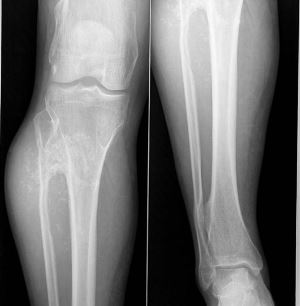

Частой локализацией наростов являются: верхняя 1/3 большеберцовой кости, нижняя 1/3 бедренной кости, верхнем отделе малоберцовой кости, верхнем конце плеча и нижнем конце предплечья. Они могут развиваться на лопаточных, ключичных, реберных костных структурах, в редких случаях – на плесневых костях и позвонках. На черепной коробке наросты не формируются. Они бывают разного размера — от горошины до большого яблока. Даже известен вариант образования экзостоза размером с детскую голову. Количество образований варьирует до нескольких сотен.

До восьмилетнего возраста костные разрастания совершенно никак о себе не извещают, но в период усиленного роста костной системы (8-18 лет) возможна активация и усиленное развитие костных образований. Особо ускоряются выросты в пубертатный период в основном на малоберцовой и большеберцовой костях, в нижнем участке бедренной кости, на лопаточной и ключичной кости.

Кисти и ступни вовлекаются в патологический процесс несколько реже и никогда – черепная коробка. Не во всех случаях возможно пальпирование их во время физикального осмотрах. Таким образом, для точного диагностирования места локализации и их количества (в том числе и внутреннего строения) понадобится рентгенографическое обследование.